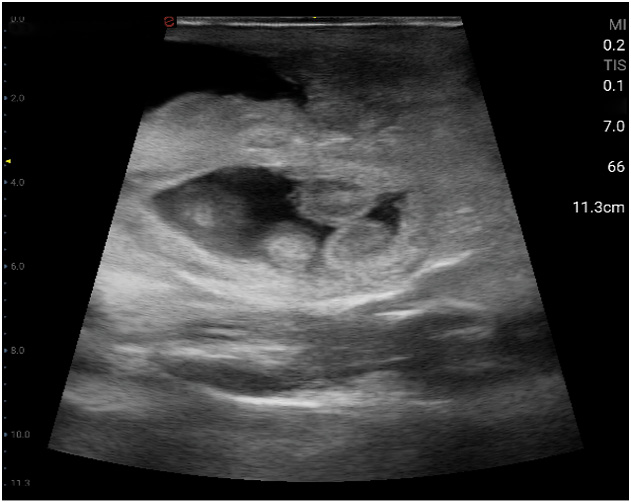

Esaote Q7 Vet er et trådløst, håndholdt ultralydapparat dedikert for veterinærer. Spesialtilpassete forhåndsinnstillinger og software og database designet for dyr. Esaote Q7 kombinerer kraften til moderne ultralydteknologi med brukervennlighet og mobilitet.

Med håndholdt ultralyd og en smartmobil/nettbrett, kan du gjøre raske og gode undersøkelser med Esaote Q7. Dets trådløse design gjør det mulig å utføre ultralydundersøkelser av høy kvalitet når som helst og hvor som helst. Alt er tilrettelagt for en vellykket undersøkelse.